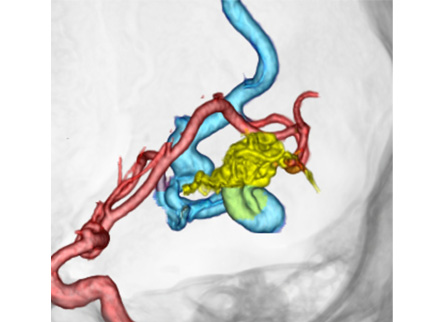

脳動静脈奇形は脳実質内に発生し、本来あるはずの動脈と静脈を繋ぐ毛細血管がないために動脈の血流がそのまま静脈へ流れてしまい、その動脈と静脈の吻合部に異常血管の集合体(ナイダス)を形成する病気です。

治療は出血を予防するために行います。摘出術や血管内治療による塞栓術、放射線治療(ガンマナイフ)を適宜組み合わせて治療を行います。

塞栓術を行うことで、ナイダスの大きさを縮小させ、摘出術の際に周囲の組織から剥離を容易にし、出血を少なくでき、手術時間の短縮や安全性向上につながります。